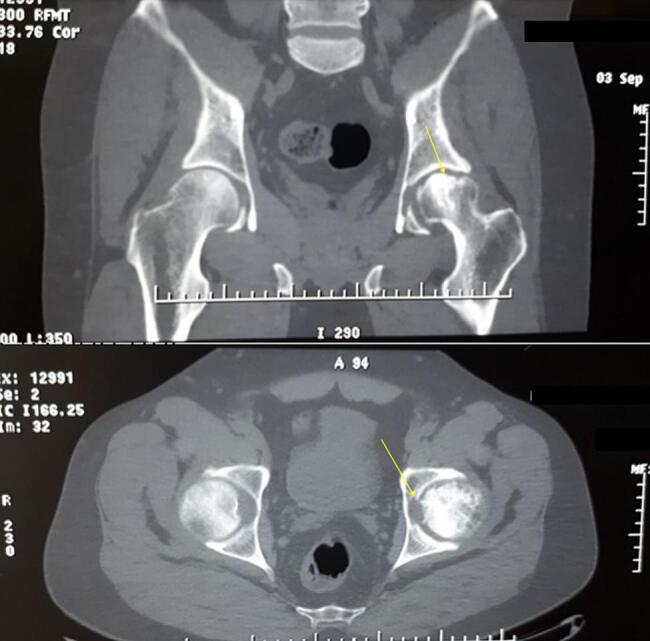

Case presentation: A 44-year-old male with femoral head avascular necrosis underwent left total hip arthroplasty. An epidural catheter was placed at the L2/3 level for postoperative pain management without complications. Two days postoperatively, the patient developed right-sided femoral nerve palsy. MRI scans revealed no spinal cord compression or hematoma. The patient's neurological symptoms began to improve five days after surgery and fully resolved by the eighth postoperative day without intervention.